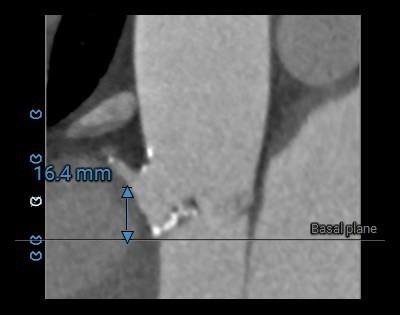

瓣上测量

2.主动脉瓣瓣环周长95.7mm,平均周长径30.5mm。